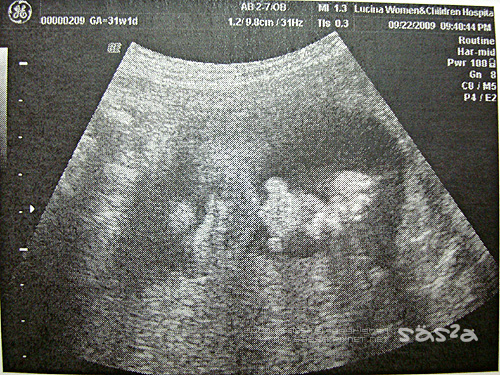

[31W]面容

眼睛像我

31W1D,昨晚見了小柚子,他跟我想像中的不一樣,希望他是單眼皮+瓜子臉,結果他是個雙眼皮大眼睛,臉形略帶四方福氣的嚴肅莊嚴的面相,我跟柚子拔互問,這孩子像誰?哈哈哈!柚子拔還說『這麼說很不敬,就覺得小柚子長得有點像彌勒佛!』XDDD。

鼻子嘴巴像拔鼻